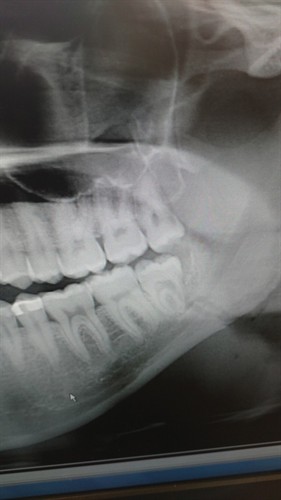

I went to the clinic at school and was referred to a maxillofacial surgeon. Upon arrival at the surgeon’s office, they shot a panoramic X-ray of my jaw. My suspicions were confirmed to nobody’s surprise; I had a fracture just anterior to the angle of the mandible right through the mandibular canal. With the 4th of July over the weekend, I wasn’t looking forward to missing out on the delicious barbequed food. Thankfully, I was able to cut the grilled chicken small enough to enjoy as well.

Here is the X-ray of my jaw. The thick line that runs through the mandible is the nerve I referred to above. Not only did the fracture go straight through the mandibular canal, it went all the way through the mandible. My basic radiology knowledge helped me decipher what was going on in this X-ray but it is pretty clear to see. I am having my jaw wired shut this week.